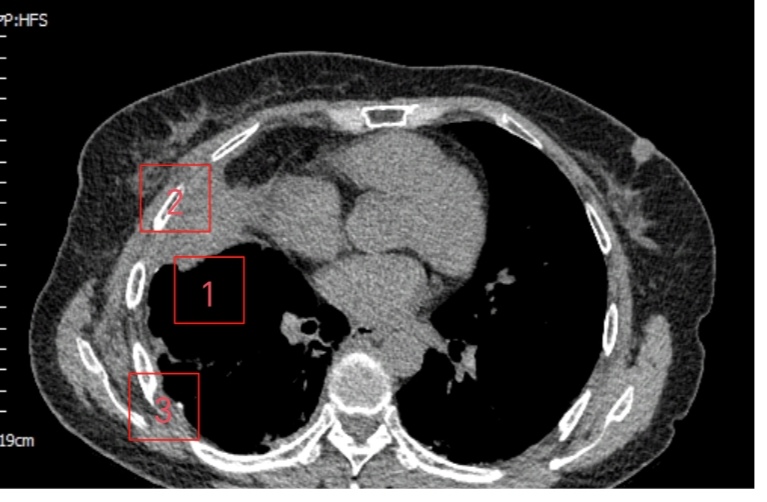

患者是一位61岁女性,诊断右侧巨型肺大疱已2年,近1周突发不明原因高热伴胸痛,体温最高达39.0℃。就诊于清华大学附属垂杨柳医院急诊科。经胸部CT检查,提示右侧巨型肺大疱(最大直径约15cm)内出现液平(最大直径约10cm),考虑疱内感染。虽经规范内科抗感染治疗,高热、胸痛症状未显著缓解,且进行性加重至无法脱离氧气支持,遂紧急转入我科进一步诊治。在胸外科主任崔健指导下,胸外科医师赵洋乐即刻联系超声科,在其精准引导下实施右侧肺大疱内及右侧胸腔脓液闭式引流术,成功引流出超过1000ml坏死液体。术后患者体温迅速恢复正常,胸痛显著缓解,脱氧状态下可自如活动。然病灶尚未根除,鉴于患者既往肺功能低下且近期高热导致营养状况不佳,需先行呼吸功能锻炼与全面营养支持,再择期手术。术前评估时,崔健围绕患者手术潜在风险,表示:1.胸腔内广泛粘连可能导致腔镜操作困难,需中转开胸;2.术中大面积渗血引发血压剧烈波动;3.肺大疱基底范围过大致无法彻底根治性切除;4.术中感染控制不佳可能引发术后严重胸腔感染及伤口不愈;5.肺功能低下致术后脱机困难。

▲闭式引流前

▲闭式引流后